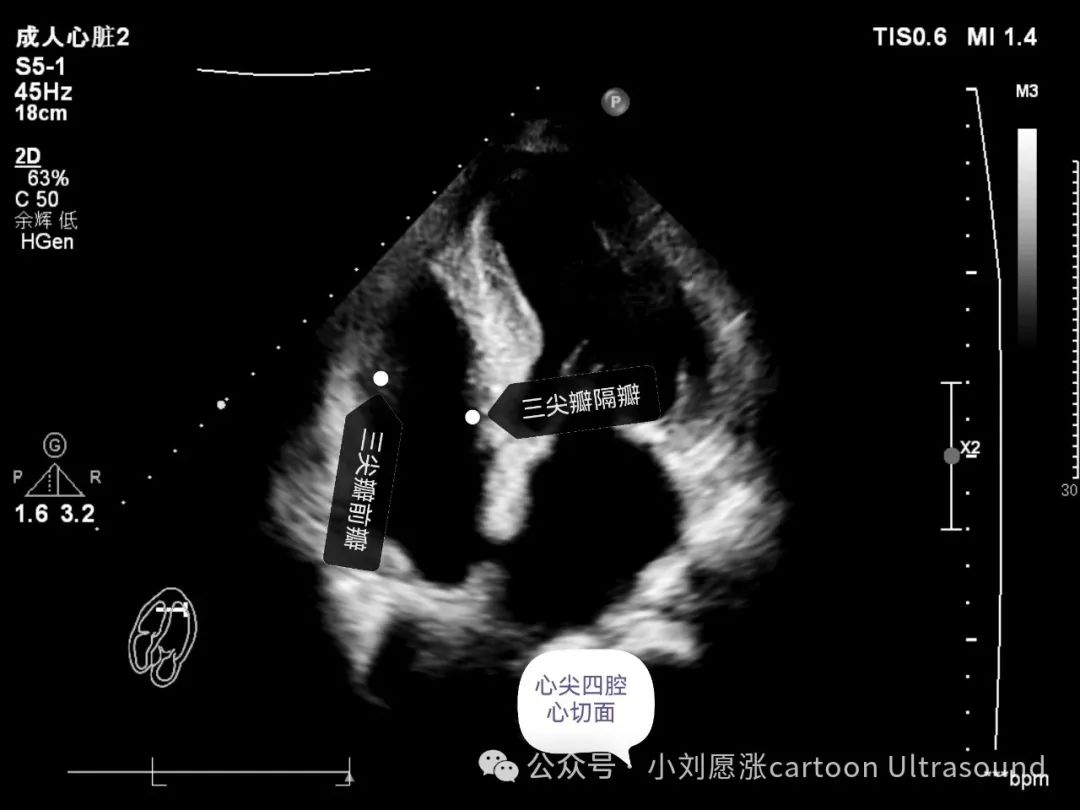

三尖瓣:3个瓣叶,前瓣、后瓣、隔瓣,后瓣只能右室流入道切面观察‍‍‍‍。